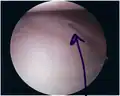

- Bankart lesion seen at arthroscopy